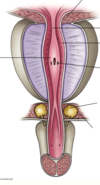

Explain the nerve supply to the muscle of the bladder.

Nerve supply motor by the parasympathetic nerves via pelvic splancnic nerves.

Sympathetic supplies the internal urethral sphincter and trigone from L1 and L2, this is more important in males because before ejaculation these will be closed off so that there is no retrograde ejaculation.

What is the blood supply to the bladder?

Lymphatics?

Blood supply comes from superior and inferior vesical artereis - branches of internal iliac.

Lymphatics follow artereis (internal and external iliac nodes).